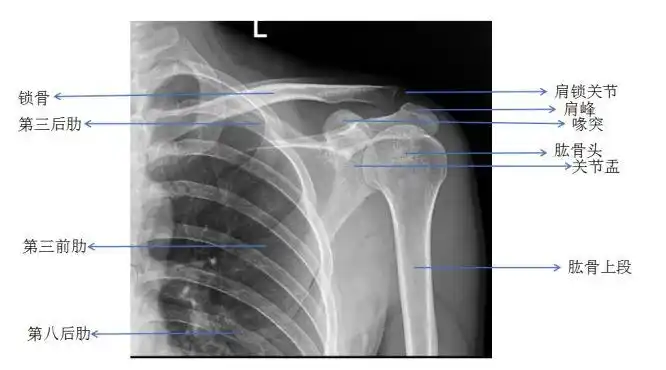

如果我们搞不清楚肩峰的位置,肩袖的组成,盂肱关节的结构的话,就很难

遇到肩部外伤时肩关节ct有必要做吗